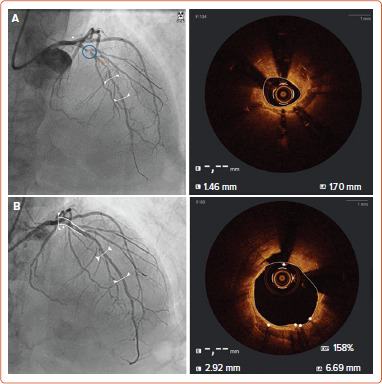

Stent underexpansion (SU) and aorto-ostial lesions (AOL) are challenging conditions commonly faced during clinical practice in the setting of percutaneous coronary interventions. Compared to other interventional settings, both SU and AOL are associated with an increased risk of immediate and late events following percutaneous coronary intervention. Several specific strategies including the systematic use of intracoronary imaging and dedicated techniques for lesions' preparation and calcium debulking have been described. This narrative review summarises the currently available options for the diagnosis and treatment of both SU and AOL, highlighting the potential benefits and limits of each technique in these specific settings.